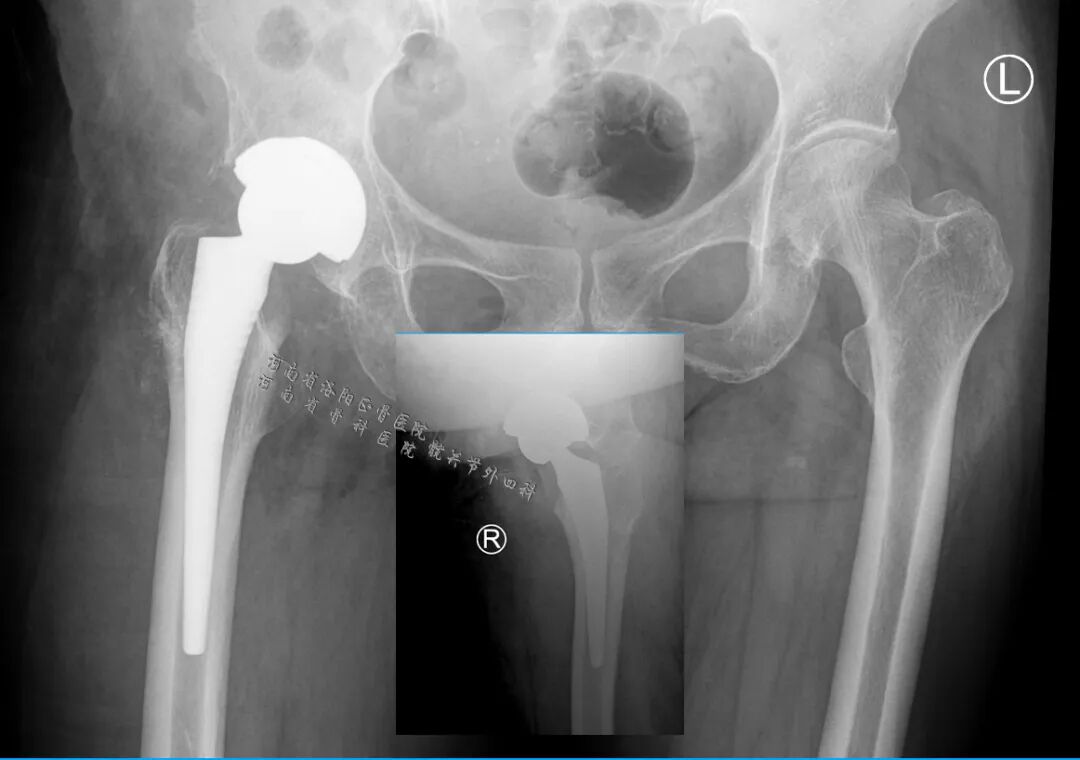

内固定完全、彻底、无损取出,为关节置换的顺利进行提供了必要条件,全陶瓷关节则令患者此生无翻修之虞。

有网友留言,考虑到长期融合以后的肌肉萎缩,陶瓷头-聚乙烯内衬更稳定,这是一个很好的建议。

但是,考虑到病人才62岁,在农村需要从事体力劳动,选择聚乙烯内衬15~20年后可能要面临一次翻修,我们还是坚持使用全陶瓷关节配置。

基于此,全陶瓷配置既能实现关节稳定,又能保证远期使用。

人工关节假体:

预期要体力劳动的年轻“老年人”还是要首选全陶瓷关节;

全陶瓷关节 ≠ 容易脱位,娴熟的技术、对骨组织、肌肉韧带的评估、术中保护、后期外展肌训练是预防脱位的关键;